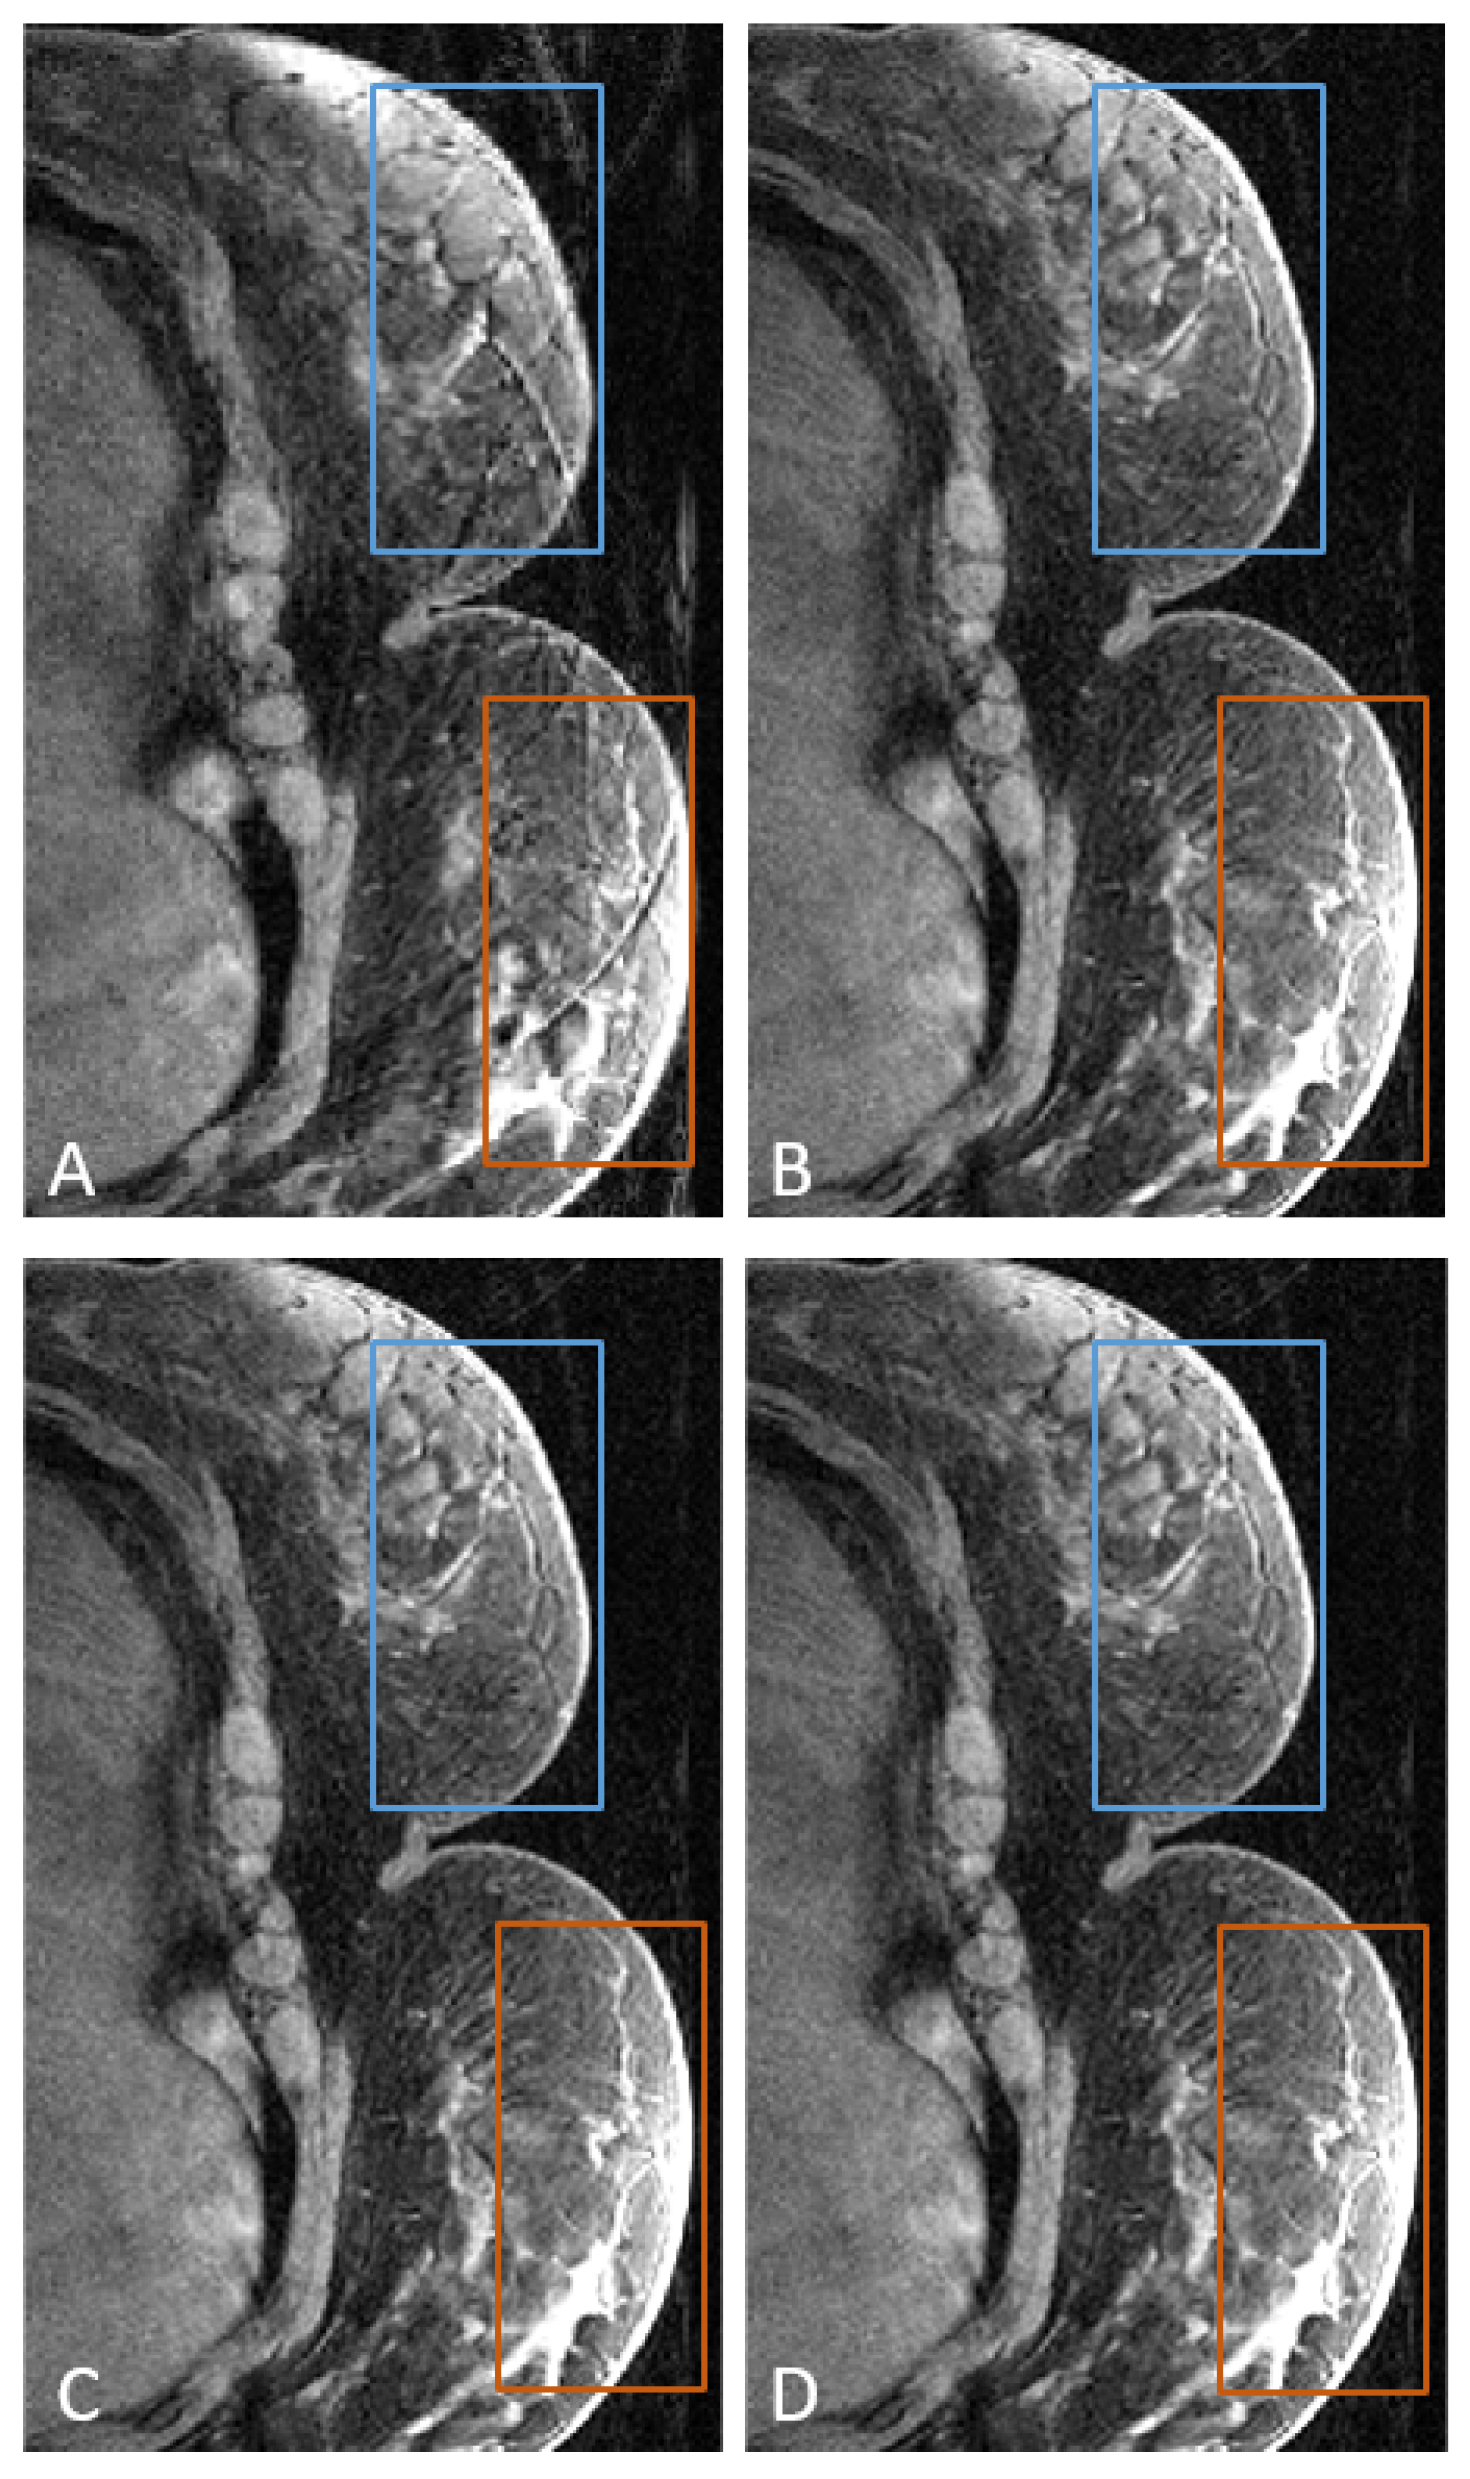

- Isaieva, K.; Meullenet, C.; Vuissoz, P.A.; Fauvel, M.; Nohava, L.; Laistler, E.; Zeroual, M.A.; Henrot, P.; Felblinger, J.; Odille, F. Feasibility of Online Non-Rigid Motion Correction for High-Resolution Supine Breast MRI. Magn. Reson. Med. 2023, 90, 2130–2143. [Google Scholar] [CrossRef] [PubMed]